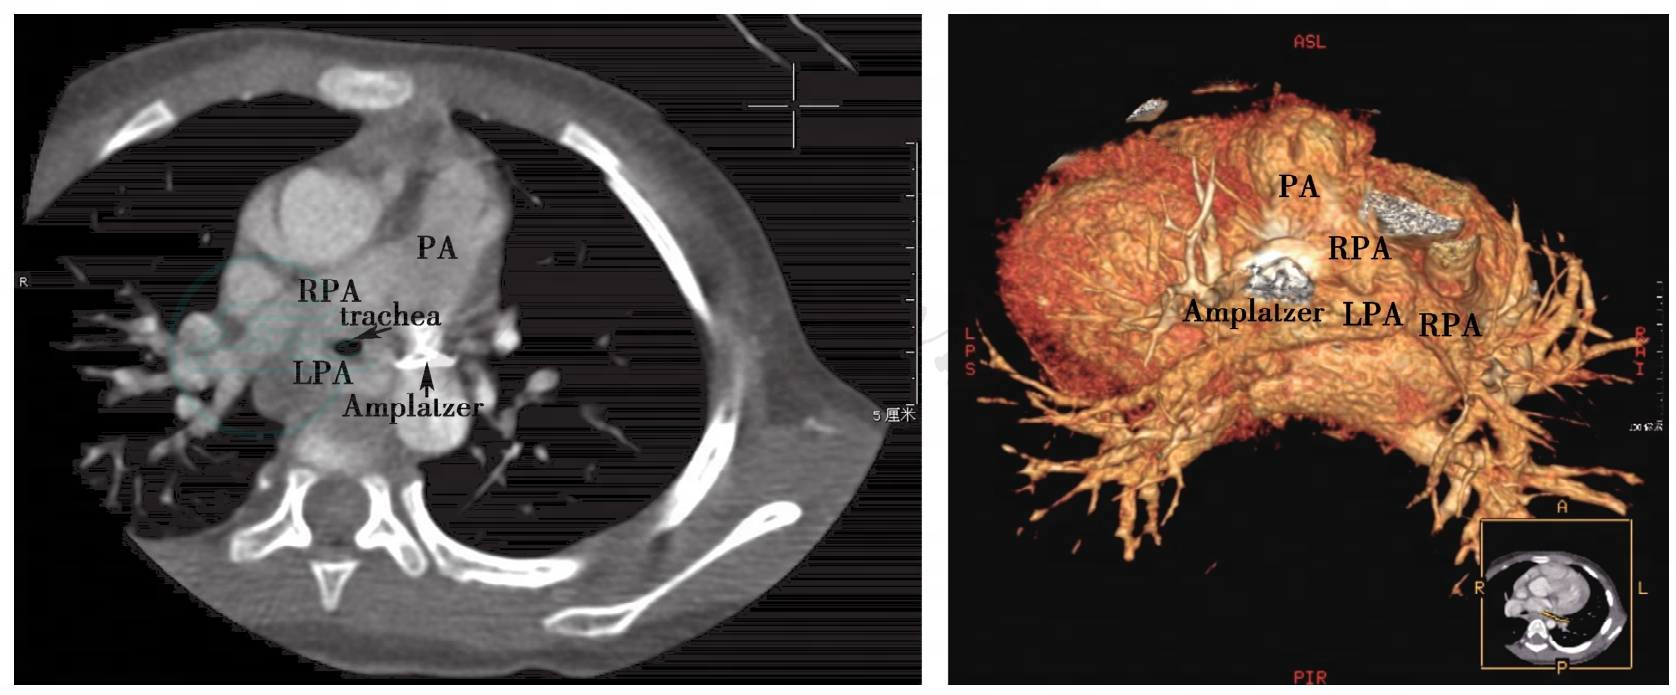

心脏CT(9月5日):肺动脉吊带,气管变窄,两侧主支气管夹角增大,左主支气管限局性狭窄;肺动脉干内径约14.3mm,右肺动脉内径约10.6mm;左肺动脉稍细,左肺动脉起自右肺动脉,绕行于气管后部向左侧走行,位于气管后部段前后径稍窄,左肺动脉起始部内径约6.9mm,气管后部内径约5.3mm;气管普遍变窄,于左肺动脉水平,气管大小约4.3mm×2.8mm;主动脉升部内径约15.6mm,弓部内径约12.6mm,降主动脉内径约10.4mm,主动脉入膈段内径约9.2mm;降主动脉位于脊柱左缘走行 (图3)。

图3 超高速CT重建示左肺动脉自右肺动脉发出并环绕气管走行

Amplatzer:动脉导管封堵伞;trachea:气管;PA:肺动脉;RPA:右肺动脉;LPA:左肺动脉